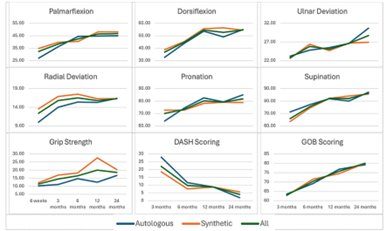

Clinical and functional outcomes

Clinical and functional outcomes demonstrated that the achieved average range of motion was sufficient for daily living activities (Figure 5). There was no statistical difference in the results between the autologous and synthetic bone graft groups. The DASH and the Green O'Brien scores showed improvement over time. At the 12- and 24-month marks, the average DASH score was 9 and 4, respectively, and 78% of the patients exhibited good to excellent function at 24 months. There was no significant donor site morbidity observed in patients who underwent autologous bone grafting.

Figure 5: The series of graphs showing the components of clinical outcomes achieved in each direction of movement (palmarflexion, dorsiflexion, ulnar deviation, radial deviation, pronation, and supination) and grip strength, and the patient reported functional scores using the DASH and Green O’Brien scores measured over time.

DASH: disabilities of the arm, shoulder, and hand